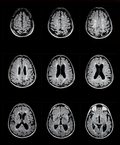

ДИАГНОСТИКА

Обнаружение в сыворотке крови различных аутоантител имеет решающее диагностическое значение для подтверждения того или иного АИЗ (аутоиммунного заболевания), определяет активность, стадию болезни и может определять прогноз (метод непрямой иммунофлюоресценции для диагностики аутоиммунных заболеваний).